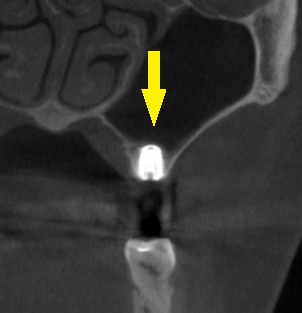

CTを撮影してみると、方向によっては、骨がありそうに見えますが、やはり十分な骨量とはいえませんでした。

ある程度の骨はありますので、ワイドインプラントを用いて、人工骨は使用せず、骨造成も行わないで、インプランント埋入が可能であると説明させていただきました。

ご納得いただけましたので、本日、ワイドショートインプラント、直径5.0mm、長さ7mmのインプラントを埋入しました。

下の写真、2段目が手術前のCT、3段目が手術後のCTです。